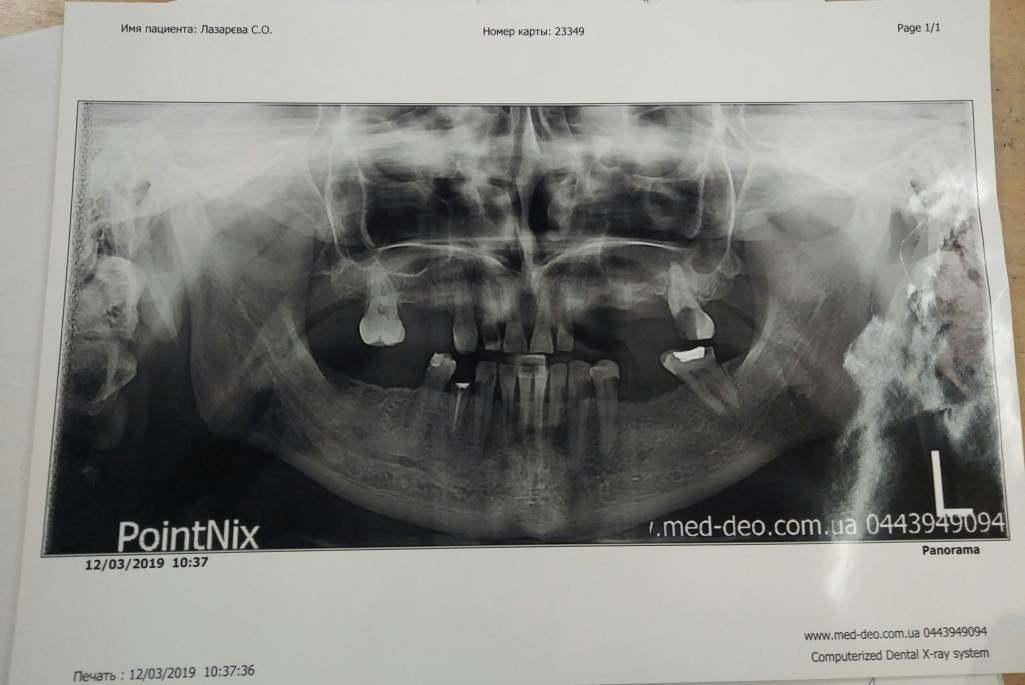

Больше половины просто высыпались, уже стоматолог просто удалил то что от них осталось. Те что есть, в ужасном состоянии. Нужна депульпацыя, лечение, протезирование.

В подтверждение моих слов прикрепляю панорамный снимок.

Дополнительно могу отправить выписку стоматолога (как и что нужно лечить, стоматолог мне все расписал)

Панорамный снимок